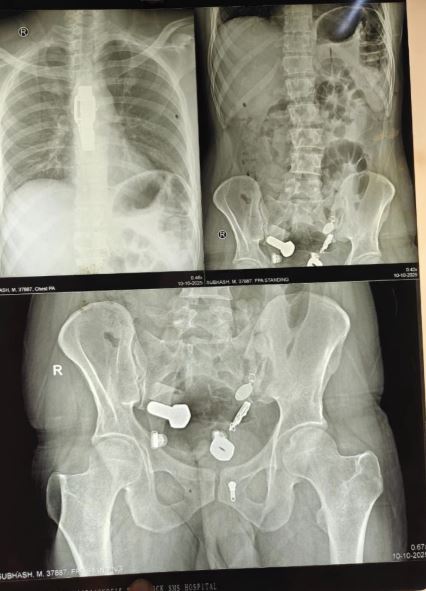

Hình ảnh chụp X-quang cho thấy khối vật thể kim loại kỳ lạ bên trong dạ dày của người đàn ông.